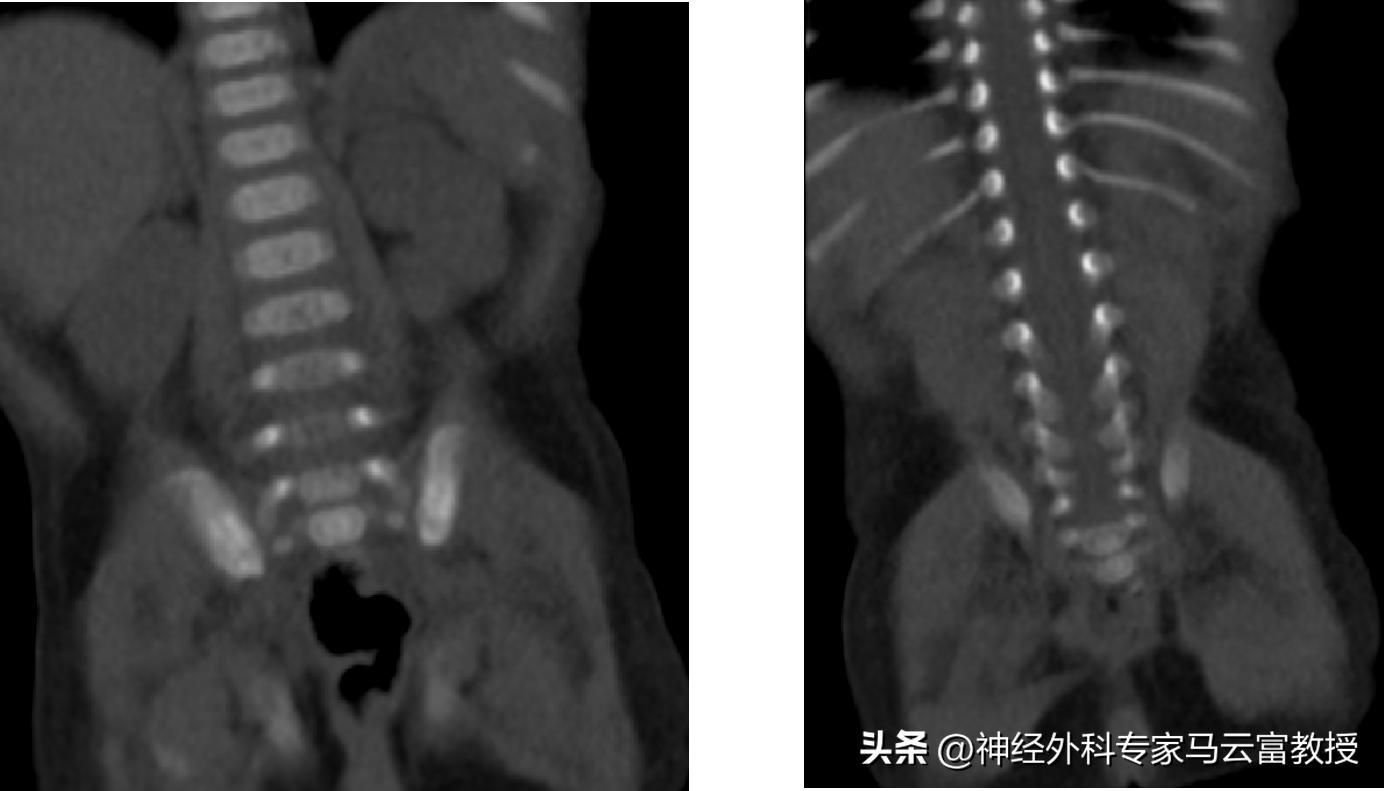

腰骶椎CT顯示脊柱裂

脊髓脊膜膨出是脊柱裂的典型表現,因寶寶脊柱椎板先天未正常融合,脊髓和脊膜會從脊柱缺損處向外膨出,形成體表可見的包塊;椎管內脂肪瘤則是椎管內長出的異常脂肪組織,會牽拉、壓迫脊髓;而脊髓栓系綜合徵,正是因脂肪瘤、膨出的脊膜等組織持續牽拉脊髓,使其無法隨寶寶身體發育正常上移,進而持續損傷神經功能,三者常合併出現,相互影響加重病情

針對脊髓脊膜膨出,手術核心是修補脊柱缺損的椎板和硬脊膜,將膨出的脊髓和脊膜回納至椎管內,嚴密縫合缺損部位,防止腦脊液漏和顱內感染,同時切除膨出的多餘囊壁;針對合併的脊髓栓系綜合徵和椎管內脂肪瘤,需同步行脊髓栓系鬆解術 + 椎管內脂肪瘤切除術,鬆解被牽拉、粘連的脊髓,切除壓迫脊髓的異常脂肪組織,解除脊髓的機械性牽拉和壓迫,從根源上阻止神經功能進一步受損。